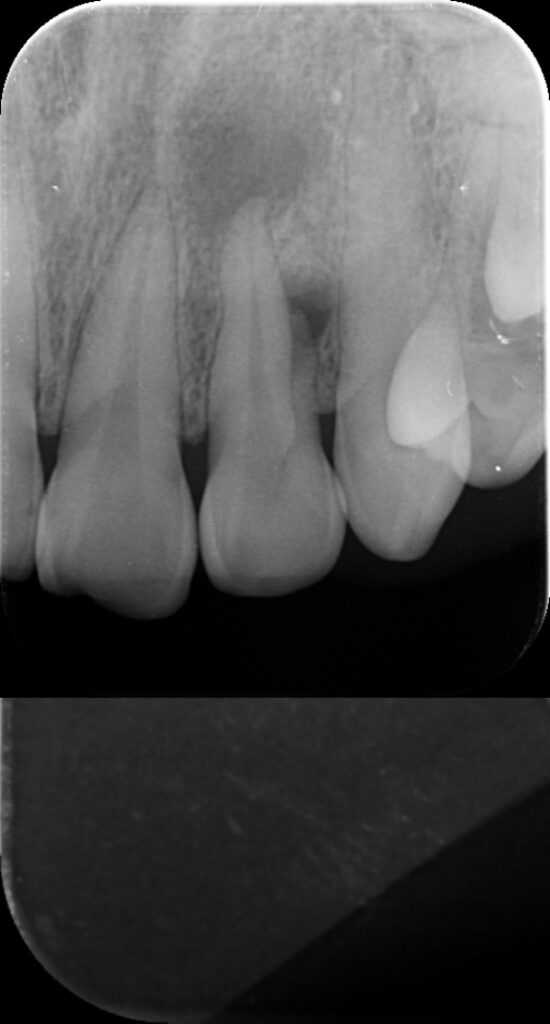

Cas très spécial = 2 lésions osseuses (rond noir)